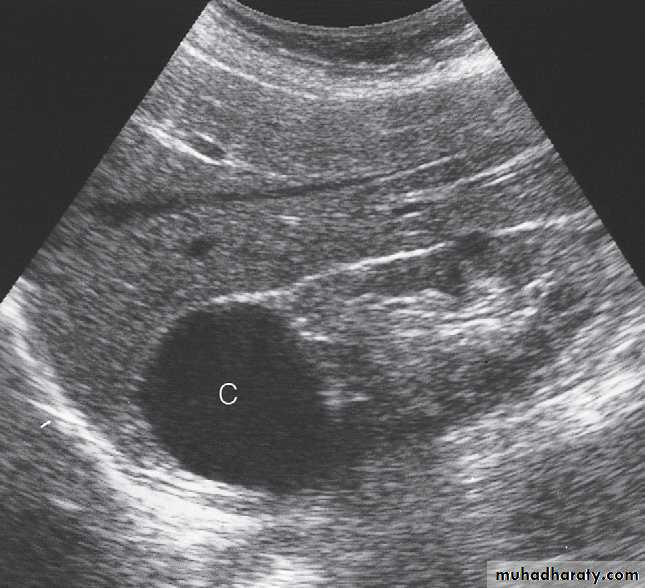

Ultrasound Dilatation of the pelvicaliceal system ( hydronephrosis ) is demonstrated sonographically as a multiloculate fluid collection in the central echo complex, caused by pooling of urine within the distended pelvis and calices .

Major DDX are multiple renal cysts. With prolonged obstruction, thinning of the cortex due to atrophy will be seen.

Renal masses are usually first detected at ultrasound examination.Ultrasound can establish whether a mass is a simple cyst and can, therefore, be ignored, or whether the lesion is solid and, therefore, is likely to be a renal carcinoma.( further evaluation with CT is indicated ) .